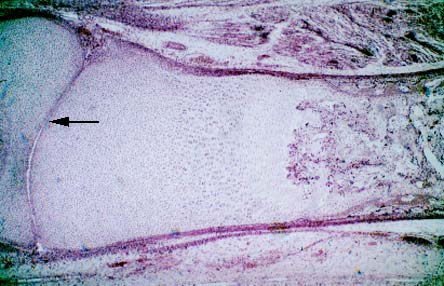

IV-31B Two articular surfaces (arrow) of adjacent bones (developing via endochondral ossification).